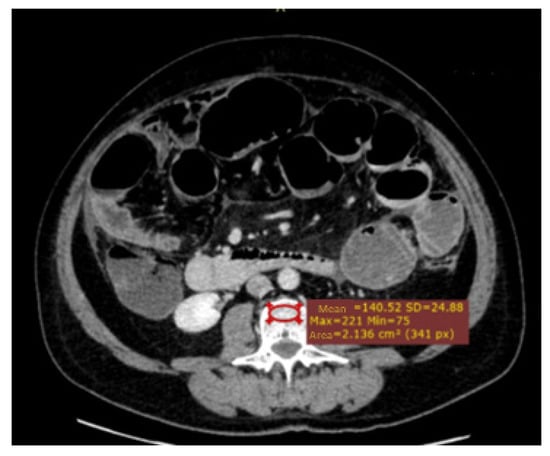

| Osteopenia (ROI at L3) | 0.725 | 0.647–0.804 | <0.001 |

| Median osteopenia in ROI at L3 (IQR) (HU) | 138.1 (102.1–181.0) | 144.0 (109.6–193.8) | 100.6 (74.6–142.5) | <0.001 |

| Number of patients with osteopenia under cut-off point | 61 (23.4%) | 38 (17.7%) | 23 (50.0%) | <0.001 |